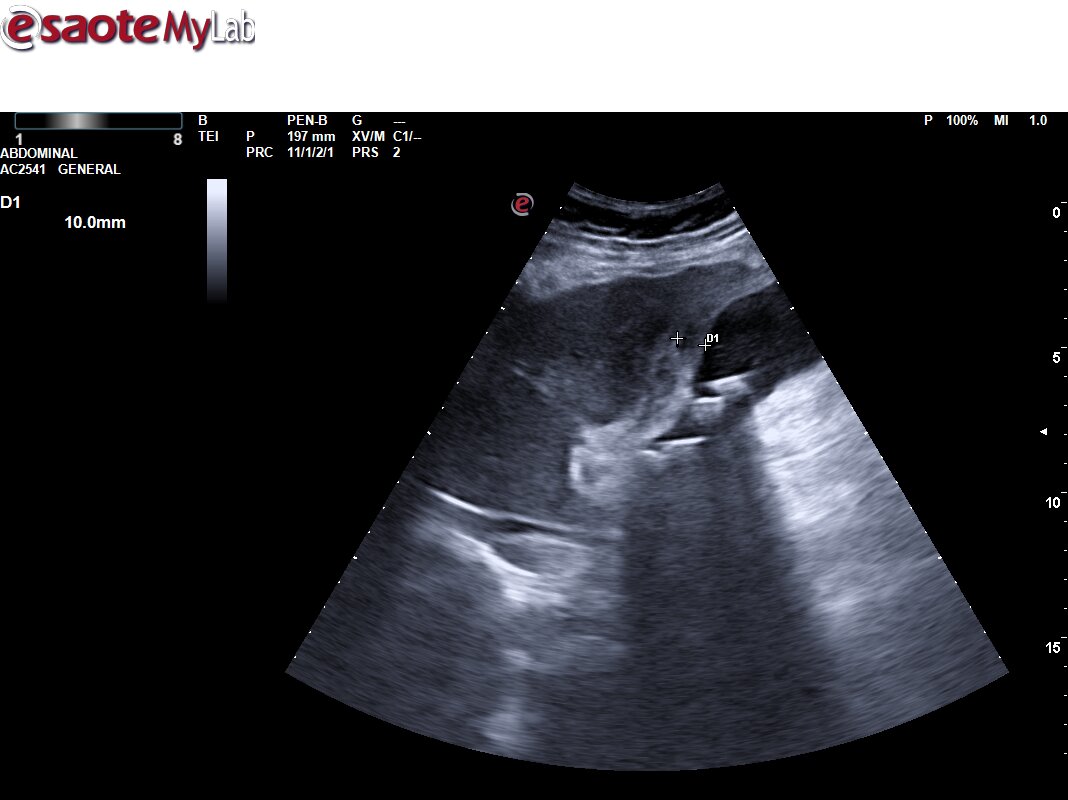

Hallazgos ecográficos

Ecografía primaria. Se aprecia vesícula con aumento de la pared de la vesícula biliar de unos 10 mm, con signos flogóticos (aumento de captación Doppler y líquido libre perivesicular), con contenido hiperecogénico en su interior con sombra posterior, y dilatación de vía intrahepática. Vía extrahepática no valorable por interposición de gases. Colecistitis. Dilatación de vía intrahepática.

Ante sospecha diagnóstica tras la ecografía de colecistitis complicada, se deriva a urgencias hospitalarias.